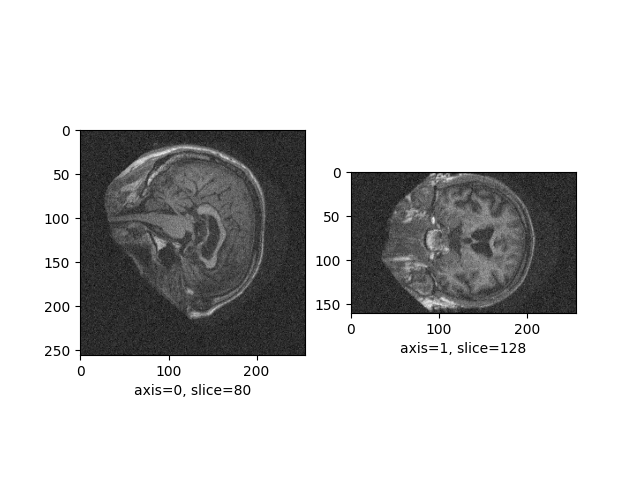

Add transforms¶

Let’s add some noise to the image:

from neuroplot.transforms import Noise

plotter = SinglePlot(axes=[0, 1], transforms=[Noise(std=200)])

plotter.plot(img_path=image_path)

<Figure size 640x480 with 2 Axes>